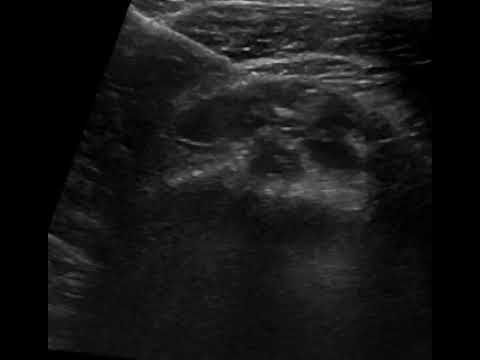

- Βελονισμός (Dry Needling) του τένοντα: Ο Βελονισμός (Dry Needling) του τένοντα είναι μία σύγχρονη, ελάχιστα επεμβατική τεχνική, κατά την οποία γίνεται θυριδοποίηση του τένοντα, δημιουργία, δηλαδή, μικρών τρυπημάτων. Σκοπός της είναι να διαταράξει τη χρόνια εκφυλιστική διαδικασία, ενθαρρύνοντας μία θεραπευτική αντίδραση στον τένοντα μέσω της τοπικής αιμορραγίας και της παραγωγής ινικών κυττάρων. Η αντίδραση αυτή οδηγεί σε επούλωση και αποκατάσταση της τενοντίτιδας. Η τεχνική ονομάζεται Dry Needling (Στεγνός Βελονισμός) για να τονιστεί ότι η τοποθέτηση της βελόνας στον τένοντα είναι ο κύριος λόγος που ο τένοντας βελτιώνεται και όχι κάποιο φάρμακο που χρησιμοποιείται. Ο βελονισμός των τενόντων είναι ασφαλής και έχει χαμηλό κίνδυνο σε σχέση με πιο επεμβατικές διαδικασίες.

- Έγχυση PRP (Platelet-Rich Plasma): Η έγχυση PRP (Platelet Rich Plasma) είναι μια επαναστατική θεραπεία για χρόνιους τραυματισμούς, η οποία βασίζεται στο πλάσμα πλούσιο σε αιμοπετάλια (Platelet-Rich Plasma/PRP). Τα αιμοπετάλια περιέχουν αυξητικούς παράγοντες που είναι σημαντικοί για την την αναπαραγωγή και επούλωση των ιστών. Με τη συγκέντρωση των αιμοπεταλίων στο PRP, ο στόχος είναι να παραδοθεί μεγαλύτερη συγκέντρωση αυτών των παραγόντων στην περιοχή που πλήττεται, προωθώντας την επούλωση του τραύματος. Η τεχνική περιλαμβάνει τη λήψη μίας μικρής ποσότητας αίματος του ασθενούς, το οποίο φυγοκεντρείται ώστε να διαχωριστεί το πλάσμα που είναι πλούσιο σε αιμοπετάλια. Το προκύπτον πλάσμα εγχέεται, με την καθοδήγηση υπερήχου, στο σημείο της βλάβης, οδηγώντας σε επιτάχυνση της θεραπείας της τενοντίτιδας. Για την ενίσχυση του θεραπευτικού αποτελέσματος, το PRP συνδυάζεται με τον Βελονισμό (Dry Needling), ο οποίος γίνεται πριν την έγχυση του πλάσματος.

- Απόλυτη Ακρίβεια: Οι υπέρηχοι επιτρέπουν στους Ιατρούς-Ακτινολόγους να εντοπίζουν με ακρίβεια τον φλεγμονώδη τένοντα και να οπτικοποιούν τη θέση της βελόνας κατά τη διάρκεια της ενέσεως. Αυτή η στοχευμένη προσέγγιση εξασφαλίζει την τοποθέτηση της ένεσης με ακρίβεια στην περιοχή που πλήττεται, βελτιώνοντας την αποτελεσματικότητά της.